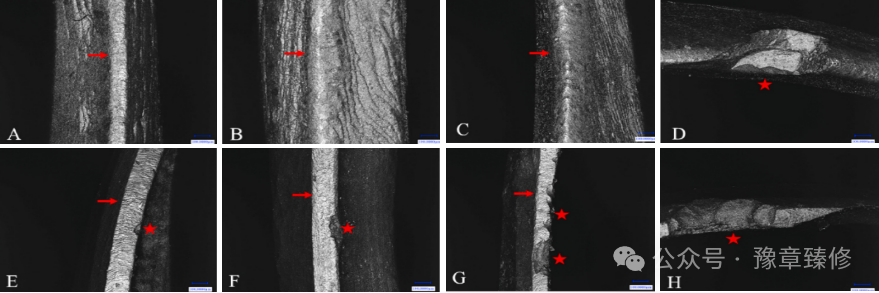

全冠增加辅助固位形(如沟、钉洞)用于短冠磨牙时,适用于𬌗龈距<4mm且剩余轴壁高度不足的活髓牙或死髓牙(图 1)。钉洞固位形通过进入牙本质(直径约1mm,深度约2mm)提供强固位力。其受力会产生拉应力,故优先用于活髓牙;死髓牙可适当加深。后牙置于牙尖间沟窝处,各钉洞方向需相互平行且与修复体就位道一致[3];沟固位形位于预备体轴壁,深1mm,龈端形成1mm肩台,形态为半圆形。其方向须与修复体就位道一致,多条沟需相互平行,且一侧轴壁必须清晰以抵抗脱位[4]。有研究对113颗冠高<5mm基牙的两年观察表明,增加固位沟可显著提升全冠固位力[5]。当短冠磨牙剩余牙体组织过薄(<1mm,无法承受沟或钉洞预备)或伴有严重牙周炎(松动度≥Ⅱ度)时,不建议采用此方法。

图1:A-D:𬌗龈距离短,近中邻面沟固位形,行金烤瓷冠修复(金属𬌗面、金属颈环设计)A:𬌗龈距离短;B:近中沟固位形;C:𬌗面观;D:侧面冠;图E-H:𬌗龈距离短,𬌗面中央钉洞固位形全瓷冠修复。E:𬌗龈距离短;F:𬌗面设置钉洞固位形;G:牙合面观;H:侧面观;